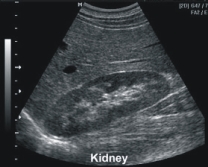

腎臟影像學檢查:包括X光檢查(來檢視腎臟的外觀、位置和大小,同時偵測腎結石的有無)及超音波掃描(透過此檢查可以得知腎臟是否萎縮、是否有腎結石、腎腫瘤、多囊性腎臟、腎髓質鈣化或腎盂水腫等)

腎臟超音波檢查